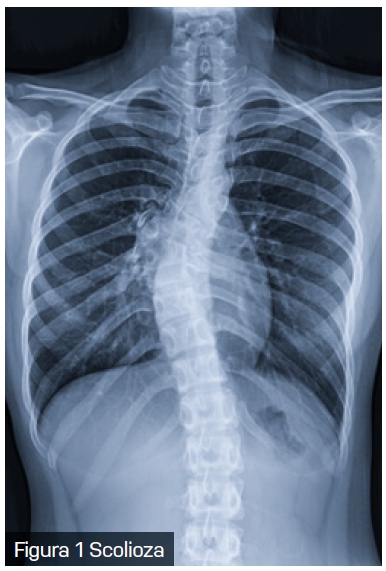

Scolioza, o deformare tridimensională a coloanei vertebrale, este o afecțiune care nu afectează doar aspectul fizic al pacientului, ci poate avea implicații semnificative și asupra sănătății respiratorii. Scolioza are o prevalență variabilă între 0,3% și 15,3% în populația generală.

Scolioza congenitală este prezentă la naștere și rezultă din malformații vertebrale sau costale, adesea asociate cu tulburări sistemice. Pe de altă parte, scolioza idiopatică, care constituie aproximativ 85% din cazuri, nu are o cauză specifică identificată și apare în perioadele de creștere rapidă. Scolioza asociată cu sindroame cunoscute este adesea subclasificată drept „scolioză sindromică”.

Modificările structurale cauzate de scolioză au un impact direct asupra mecanicii respiratorii. Deformarea coloanei vertebrale și a toracelui reduce complianța peretelui toracic, limitează mobilitatea coastelor și afectează forța musculaturii intercostale. Aceste schimbări conduc la o scădere a volumului pulmonar și determină compresia focală a căilor respiratorii. În special la copiii cu scolioză cu debut precoce, limitarea creșterii normale a toracelui și a plămânilor poate avea consecințe pe termen lung asupra dezvoltării respiratorii.

În practica clinică, pacienții cu scolioză pot dezvolta un tipar de respirație rapidă și superficială, în încercarea de a compensa rigiditatea peretelui toracic. Această adaptare conduce la o scădere a capacității de efort și la apariția dispneei de efort, una dintre primele manifestări clinice ale scoliozei. Implicarea coloanei toracice (singură sau în combinație cu segmentul lombar) în scolioză este responsabilă pentru complicațiile respiratorii și cardiovasculare, iar distorsiunea cutiei toracice crește efortul respirator necesar.

Datorită interconexiunilor complexe dintre coloana vertebrală, stern și coaste, mișcarea și rotația vertebrelor în cazul scoliozei au un impact semnificativ asupra formei toracelui, generând o latură convexă și una concavă. Pe lângă severitatea curbei coloanei vertebrale, vârsta pacientului joacă un rol în distribuția inegală a gazelor alveolare. Reducerea capacității de a efectua efort fizic la copiii cu scolioză nu se datorează doar scăderii capacității respiratorii, ci și diminuării abilității inimii de a se adapta la cerințele metabolice crescute. De asemenea, micșorarea diametrului anteroposterior al toracelui la acești copii determină o deplasare a inimii, afectând astfel funcționarea acesteia.